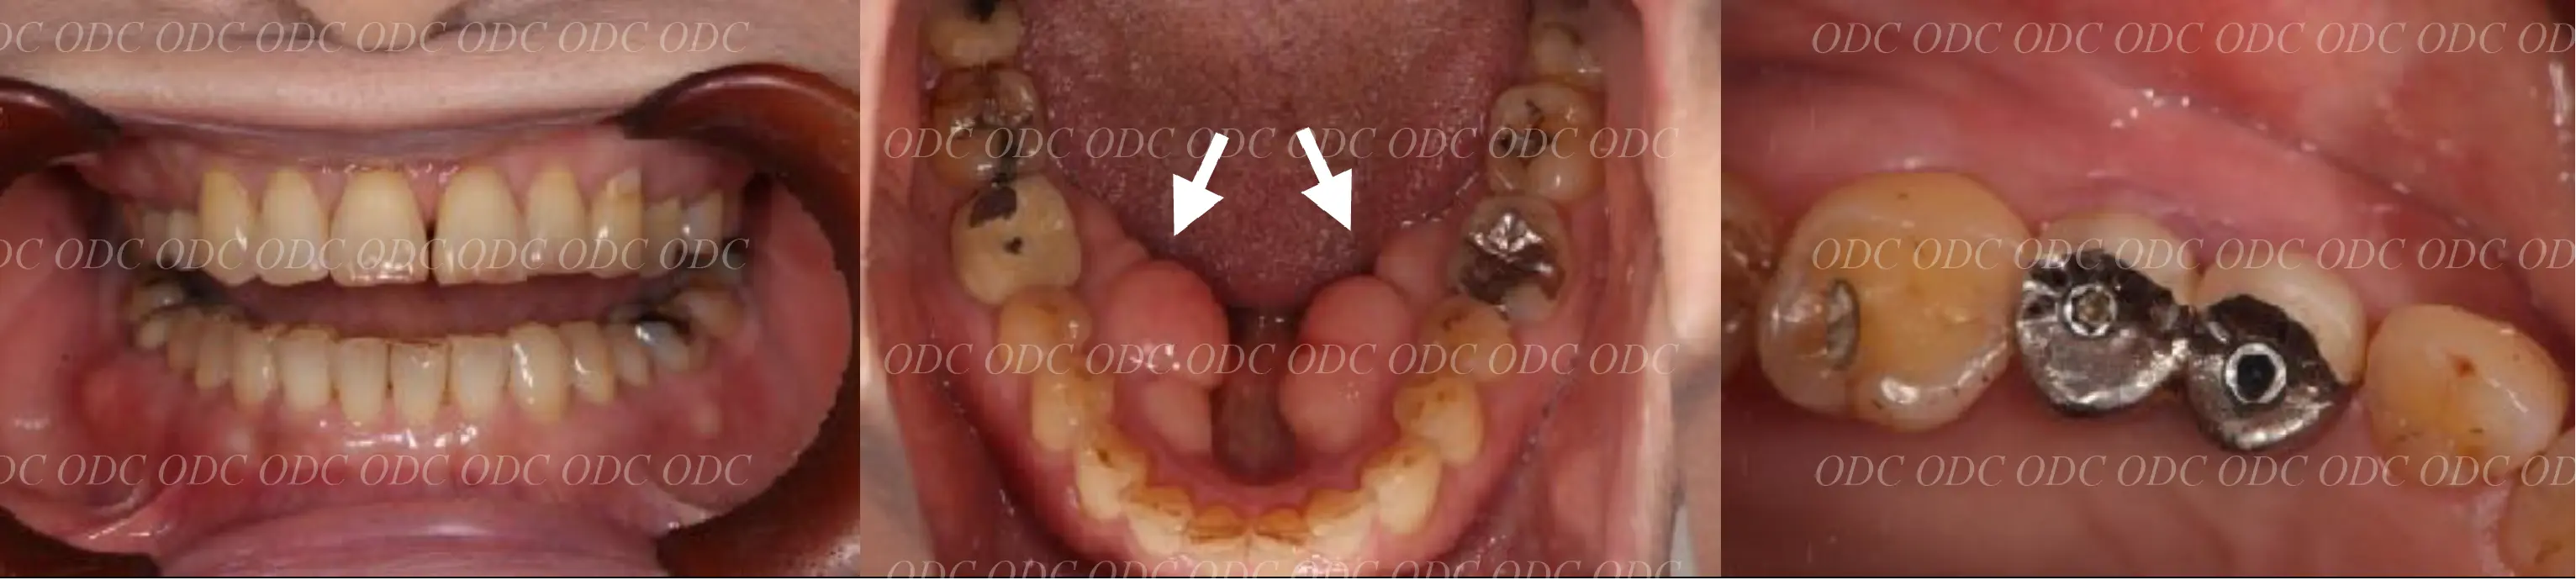

包括的治療 症例

2011年、噛めないという主訴で65歳の男性が来院されました。

全顎的な治療を希望されていましたので、口腔内はもちろん骨格・顔貌・顎関節の診断を行い治療目標を設定致しました。

上顎天然歯に関しては矯正治療、下顎にはフルマウスのインプラント治療を計画致しました。

顎関節の安定を確認した後、矯正治療とインプラント治療を並行して行いました。

約3年の治療期間を経て、計画通りの満足のいく結果を獲得することができました。

2014年、治療終了時の口腔内の状態です。

インプラント上部構造はCADCAMによって作成されたジルコニアの上部構造です。

2024年、治療終了後約10年が経過いたしました。

顎関節を考慮した包括的な治療を行うことで咬合状態(噛み合わせ)は現在もとても安定した状態です。